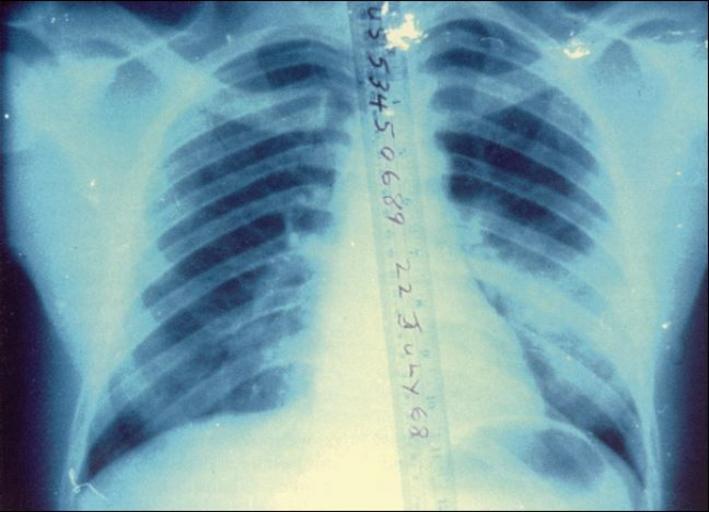

| Keywords: Blast lung-chest radiograph.jpg en Blast lung This chest roentgenogram of a soldier who was injured by blast shows bilateral infiltrates from pulmonary contusion The patient survived without sequelae ~ U S Army Wound Data and Munitions Effectiveness Team WDMET The WDMET database was comprised from the cases of 7 989 wounded American soldiers in Vietnam from 1967 through 1969 22 July 1968 2013-04-29 14 19 35 From the Textbook of Military Medicine part I volume 5 page 302 figure 9-2 http //webapp1 dlib indiana edu/cgi-bin/virtcdlib/index cgi/4931363/FID1/DATA/operationalmed/Military 20Medicine/Blast 20Injuries/Blast 20Injuries- 20Recognition 20and 20Management htm United States Army Medical Department PD-USGov Uploaded with UploadWizard Blast injuries Lungs | ||||